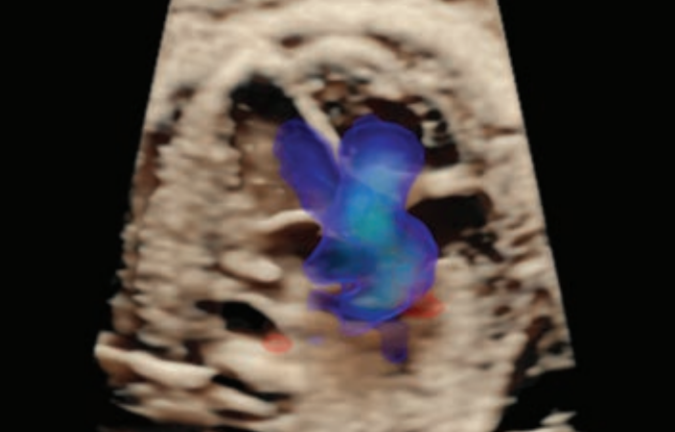

- Su tecnología HDlive Flow te va a ayudar a ver estructuras vasculares con mayor realismo anatómico.